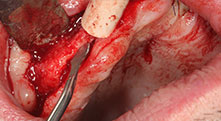

Bratu: We routinely use the instruments for harvesting bone blocks and splitting alveolar ridges. We also use the Piezomed B6/B7 for osteotomy of impacted teeth and removing failed implants. All indications that require deep, clean cuts.

Could you describe briefly, for example, your procedure for mobilizing bone blocks for transplantation?

Bratu: We prefer to harvest bone from the external oblique ridge of the posterior mandible, not from the interforaminal region. After the soft-tissue incision, we use the new saws to define the amount of bone to harvest. With this approach, we also use them for the entire preparation in almost 80% of cases. We may also use other piezo instruments and then at the end a chisel to mobilize the block. We find that this is a very effective surgical technique.

What do you consider the advantages of piezo surgery in relation to oral tissue?

Bratu: I consider piezo surgery a great leap forward in oral surgery. The technique makes bone preparation safer and easier. Little bone is lost, for example in extractions. This is very important in the aesthetic zone, particularly if immediate implantation is planned. Piezo surgery is also safer for soft tissue: injuries to membranes in the sinus are basically history, as are nerve injuries when bone blocks are being harvested. Data indicating reduced postoperative swelling and pain are also available. Piezo surgery is also ideal for preparation of sinus septa. And last but not least, our patients benefit from the atraumatic nature of this technology.